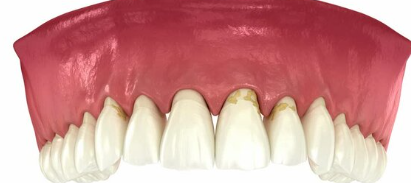

2. 잇몸이 붓고 붉다 – 정상적인 핑크빛이 아니다

염증이 심해질수록 잇몸은 단단함을 잃고 부풀어 오르며 붉게 변색됩니다.

- 치아 주변 잇몸이 탱탱하게 부어오름

- 밝은 분홍이 아닌 짙은 적색 또는 자주색

- 음식물 씹을 때 불편함 발생

▶ 부기와 발적(붉어짐)은 급성 치주염의 대표적인 징후로, 치료가 필요한 시점입니다.

4. 잇몸이 내려가고 치아가 길어 보인다 – 잇몸 퇴축 현상

잇몸뼈가 녹아내리면, 잇몸이 치아뿌리 쪽으로 물러나면서 치아가 길어 보이는 현상이 나타납니다.

- 거울로 보면 치아가 평소보다 길게 보임

- 잇몸 경계가 울퉁불퉁하고 균일하지 않음

- 찬물 마실 때 시림이 심해짐

▶ 치아가 길어지는 건 단순한 미용 문제가 아닌 치아지지 구조 약화의 증거입니다.